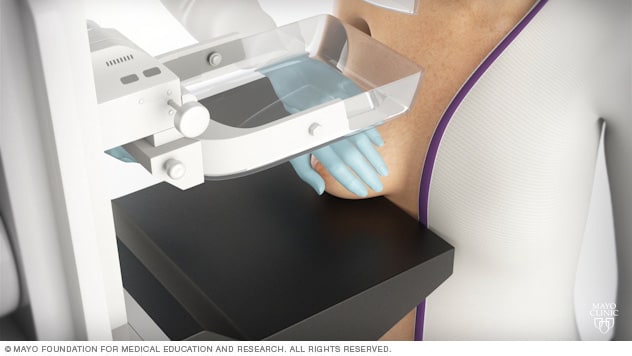

Что такое маммография: важность, процесс и результаты

Раздел: Необычные решения